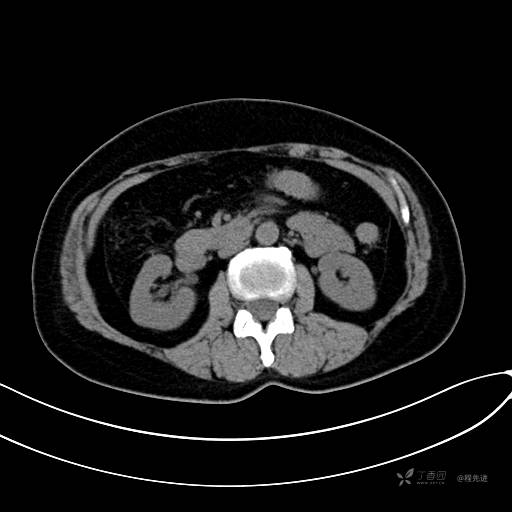

CT增强门脉期